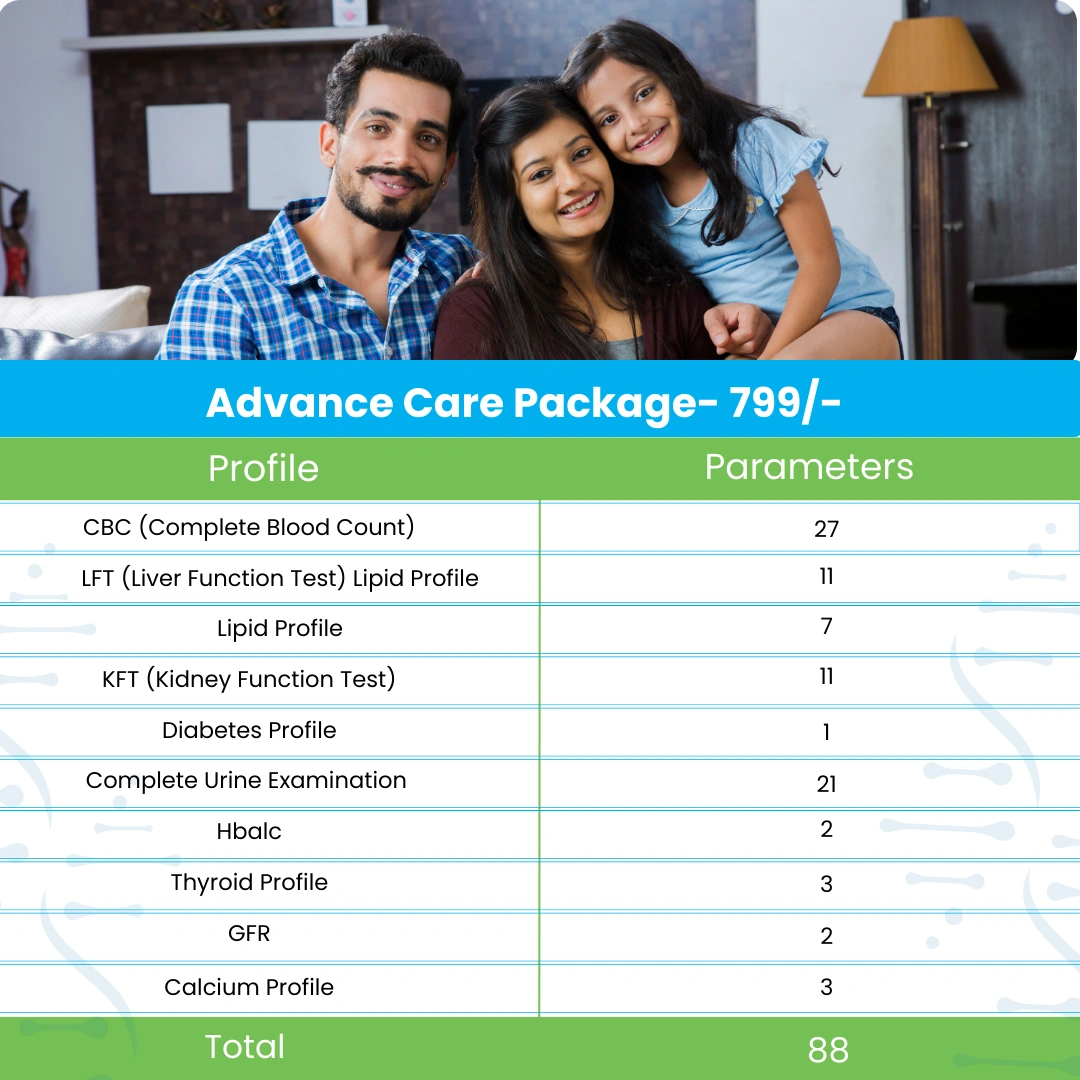

Packages

Packages